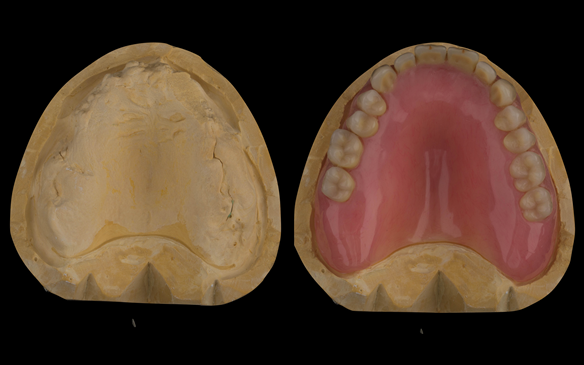

- Extraction of all upper teeth and LR5 and LL4 and fitting of immediate acrylic based (Mk 1) dentures - complete upper and lower partial

- Reviews of the immediate dentures and relines as needed over 9 - 12 months

- Definitive dentures (Mk 2) – complete upper metal reinforced and lower cobalt chromium based partial of hygienic Scandinavian design to be made 9 - 12 months after extractions of all upper teeth and LR5 and LL4

The clinical situation and treatment process is shown in detail below with photographs.